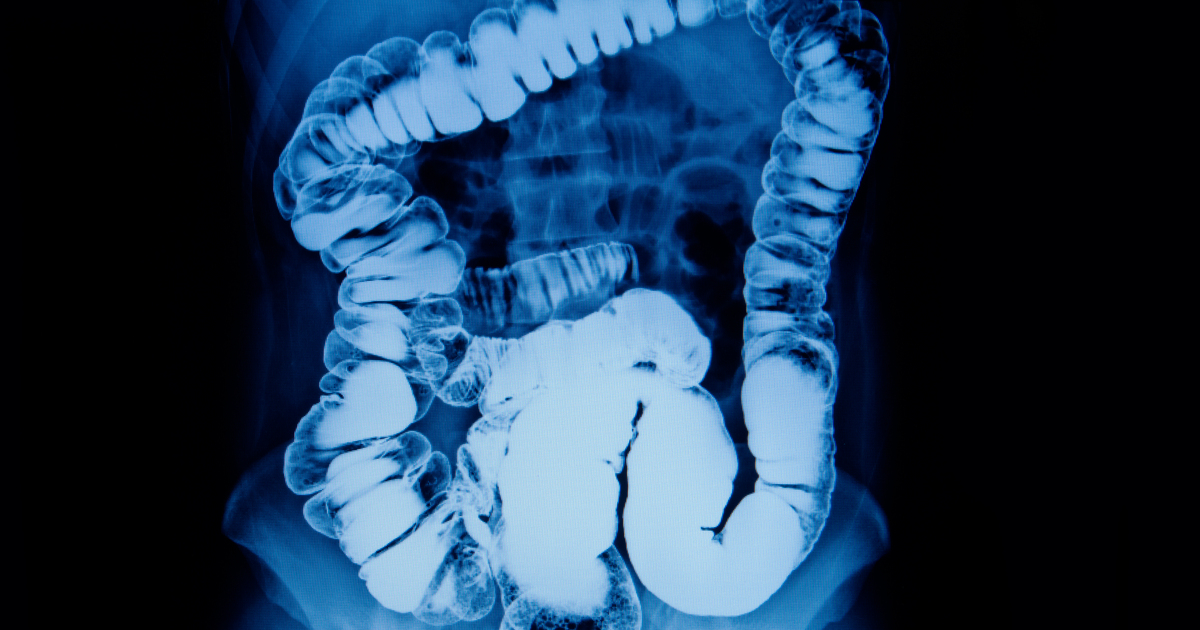

Xray imaging of colitis barium enema contrast study Stock Photo Adobe Ischemic Colitis Barium Enema However, few publications have addressed the sonographic findings of this. Barium contrast enema may suggest colon ischemia with the thumbprint sign seen in 75% of patients. Barium enema should be avoided in cases where there is a suspicion of gangrene or perforation. Ischemic colitis is the most common form of gi ischemia; Barium enema also makes the later. The majority. Ischemic Colitis Barium Enema.